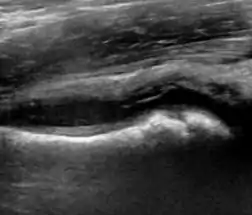

During childhood, ultrasound is a quick method to assess hip pain and quite often may be used to avoid use of irradiating techniques, such as radiography or CT. Ultrasound allows evaluation of joint effusion, synovial thickening and neovascularity, the bone/cartilage contour, and the femoral head-neck alignment. Although sonography is extremely sensitive in detecting increased synovial fluid, it is nonspecific and cannot be used with accuracy to determine the type of fluid. Transient synovitis of the hip, despite being the most frequent cause of pain in children between 3 and 10 years, remains a diagnosis of exclusion. It usually shows anechoic fluid, but echogenic fluid can also be found. The effusion is considered pathologic when it is measured at >2 mm in thickness. The differential diagnosis is wide, including osteomyelitis, septic arthritis, primary or metastatic lesions, LCPD, and SCFE. Discrimination from septic arthritis is challenging, often requiring joint aspiration. In septic arthritis, US is able to demonstrate a hip joint effusion, synovial thickening, and cartilage damage, although the appearances are nonspecific.[1]

Figure 12:

Normal ultrasound appearance of the femoral head-neck junction.

Joint effusion in transient synovitis of the hip.

Flattening of the femoral head in a patient with Perthes disease.

Step in the femoral head-neck junction in a patient with SCFE.